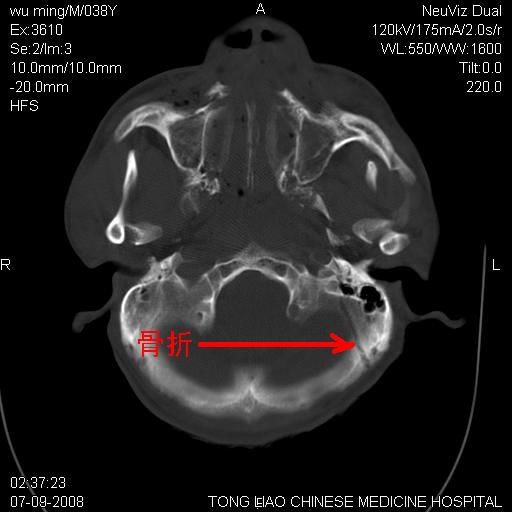

颅底多发骨折。

颅底多发骨折.上颌骨多发骨折

右侧眼眶,上颌骨,鼻骨、上颌窦等很多

考虑:面骨、颅底骨多发骨折,颅内高压(脑肿胀)。

面骨、颅底骨多发骨折,右侧硬膜下小血肿,弥漫轴索损伤,死亡原因可能是多种因素致。

1)颅底骨及颌面骨多发性骨折。2)副鼻窦及双侧鼻腔积血。

颅底骨折,窦腔内积血。考虑死亡原因为脑水肿压迫脑干或因大量失血死亡。

前颅窝颅底骨折,死的原因应该从头部来看不用说就是重度颅脑损伤。

颅底、上颌骨,双侧颧骨多发骨折。死因或许与此无关,是否有腹部脏器损伤有关